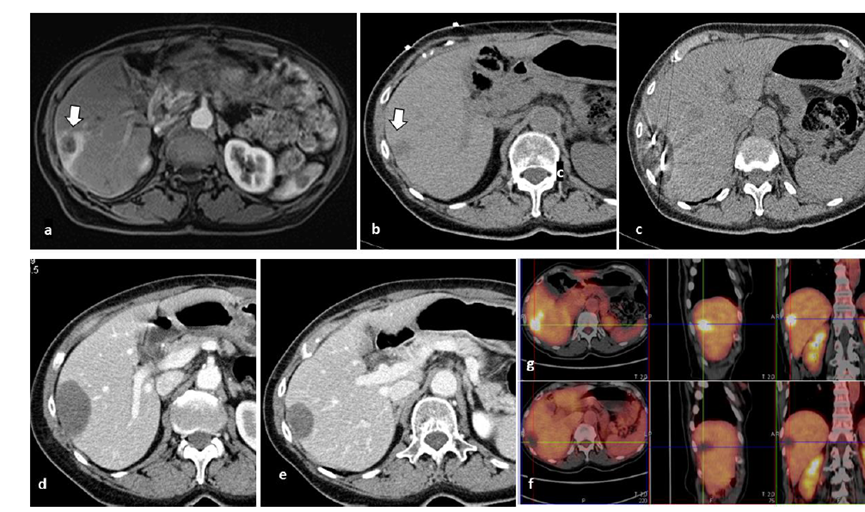

冷凍消融膽囊附近腫瘤病灶

(A)動(dòng)脈期 MRI 顯示膽囊附近有外周增強病變(箭頭)。

(B)手術(shù)過(guò)程中 CT 顯示冷凍探針位于病灶內。

(C)消融后,術(shù)后 1 個(gè)月CT 顯示完全消融(箭頭)。

(D)消融手術(shù)后 1 個(gè)月CT 顯示完全消融。